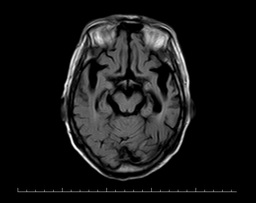

之后,医生为殷阿姨完善了其他检查,颅脑海马+MRA显示:1.双侧基底节区多发腔梗灶;2.脑白质变性;3.幕上(包括双侧海马)弥漫性脑萎缩,以左侧颞叶为著; 4.脑MRA检查提示脑动脉粥样硬化(图一)。颅脑ASL提示:全脑3D-ASL序列检查提示左侧额颞顶枕叶及右侧颞顶枕叶多发稍低灌注区,以左侧大脑半球为主(图二)。

头颅MRI T2图一 MRI FLAIR 图一